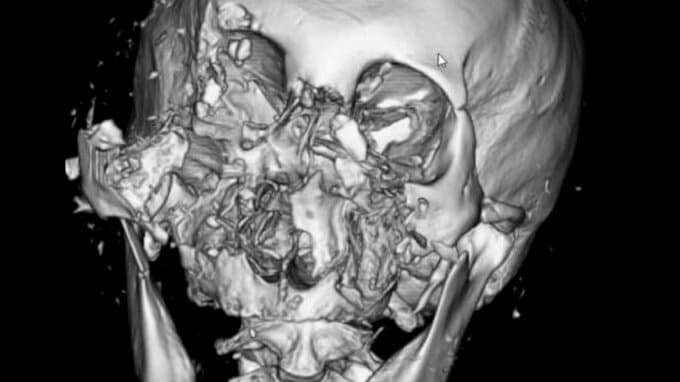

クマに襲われた患者のCT画像では、顔の骨が激しく砕けているのが分かります。

負傷者の9割が顔面に深い傷を負うというクマ外傷。あごや鼻の骨が折れたり、顔が引き裂かれたり。

クマの攻撃で傷を負った部位のうち、顔面が90%、続いて腕70%、頭部60%、脚40%と上半身が圧倒的に多くなっています。